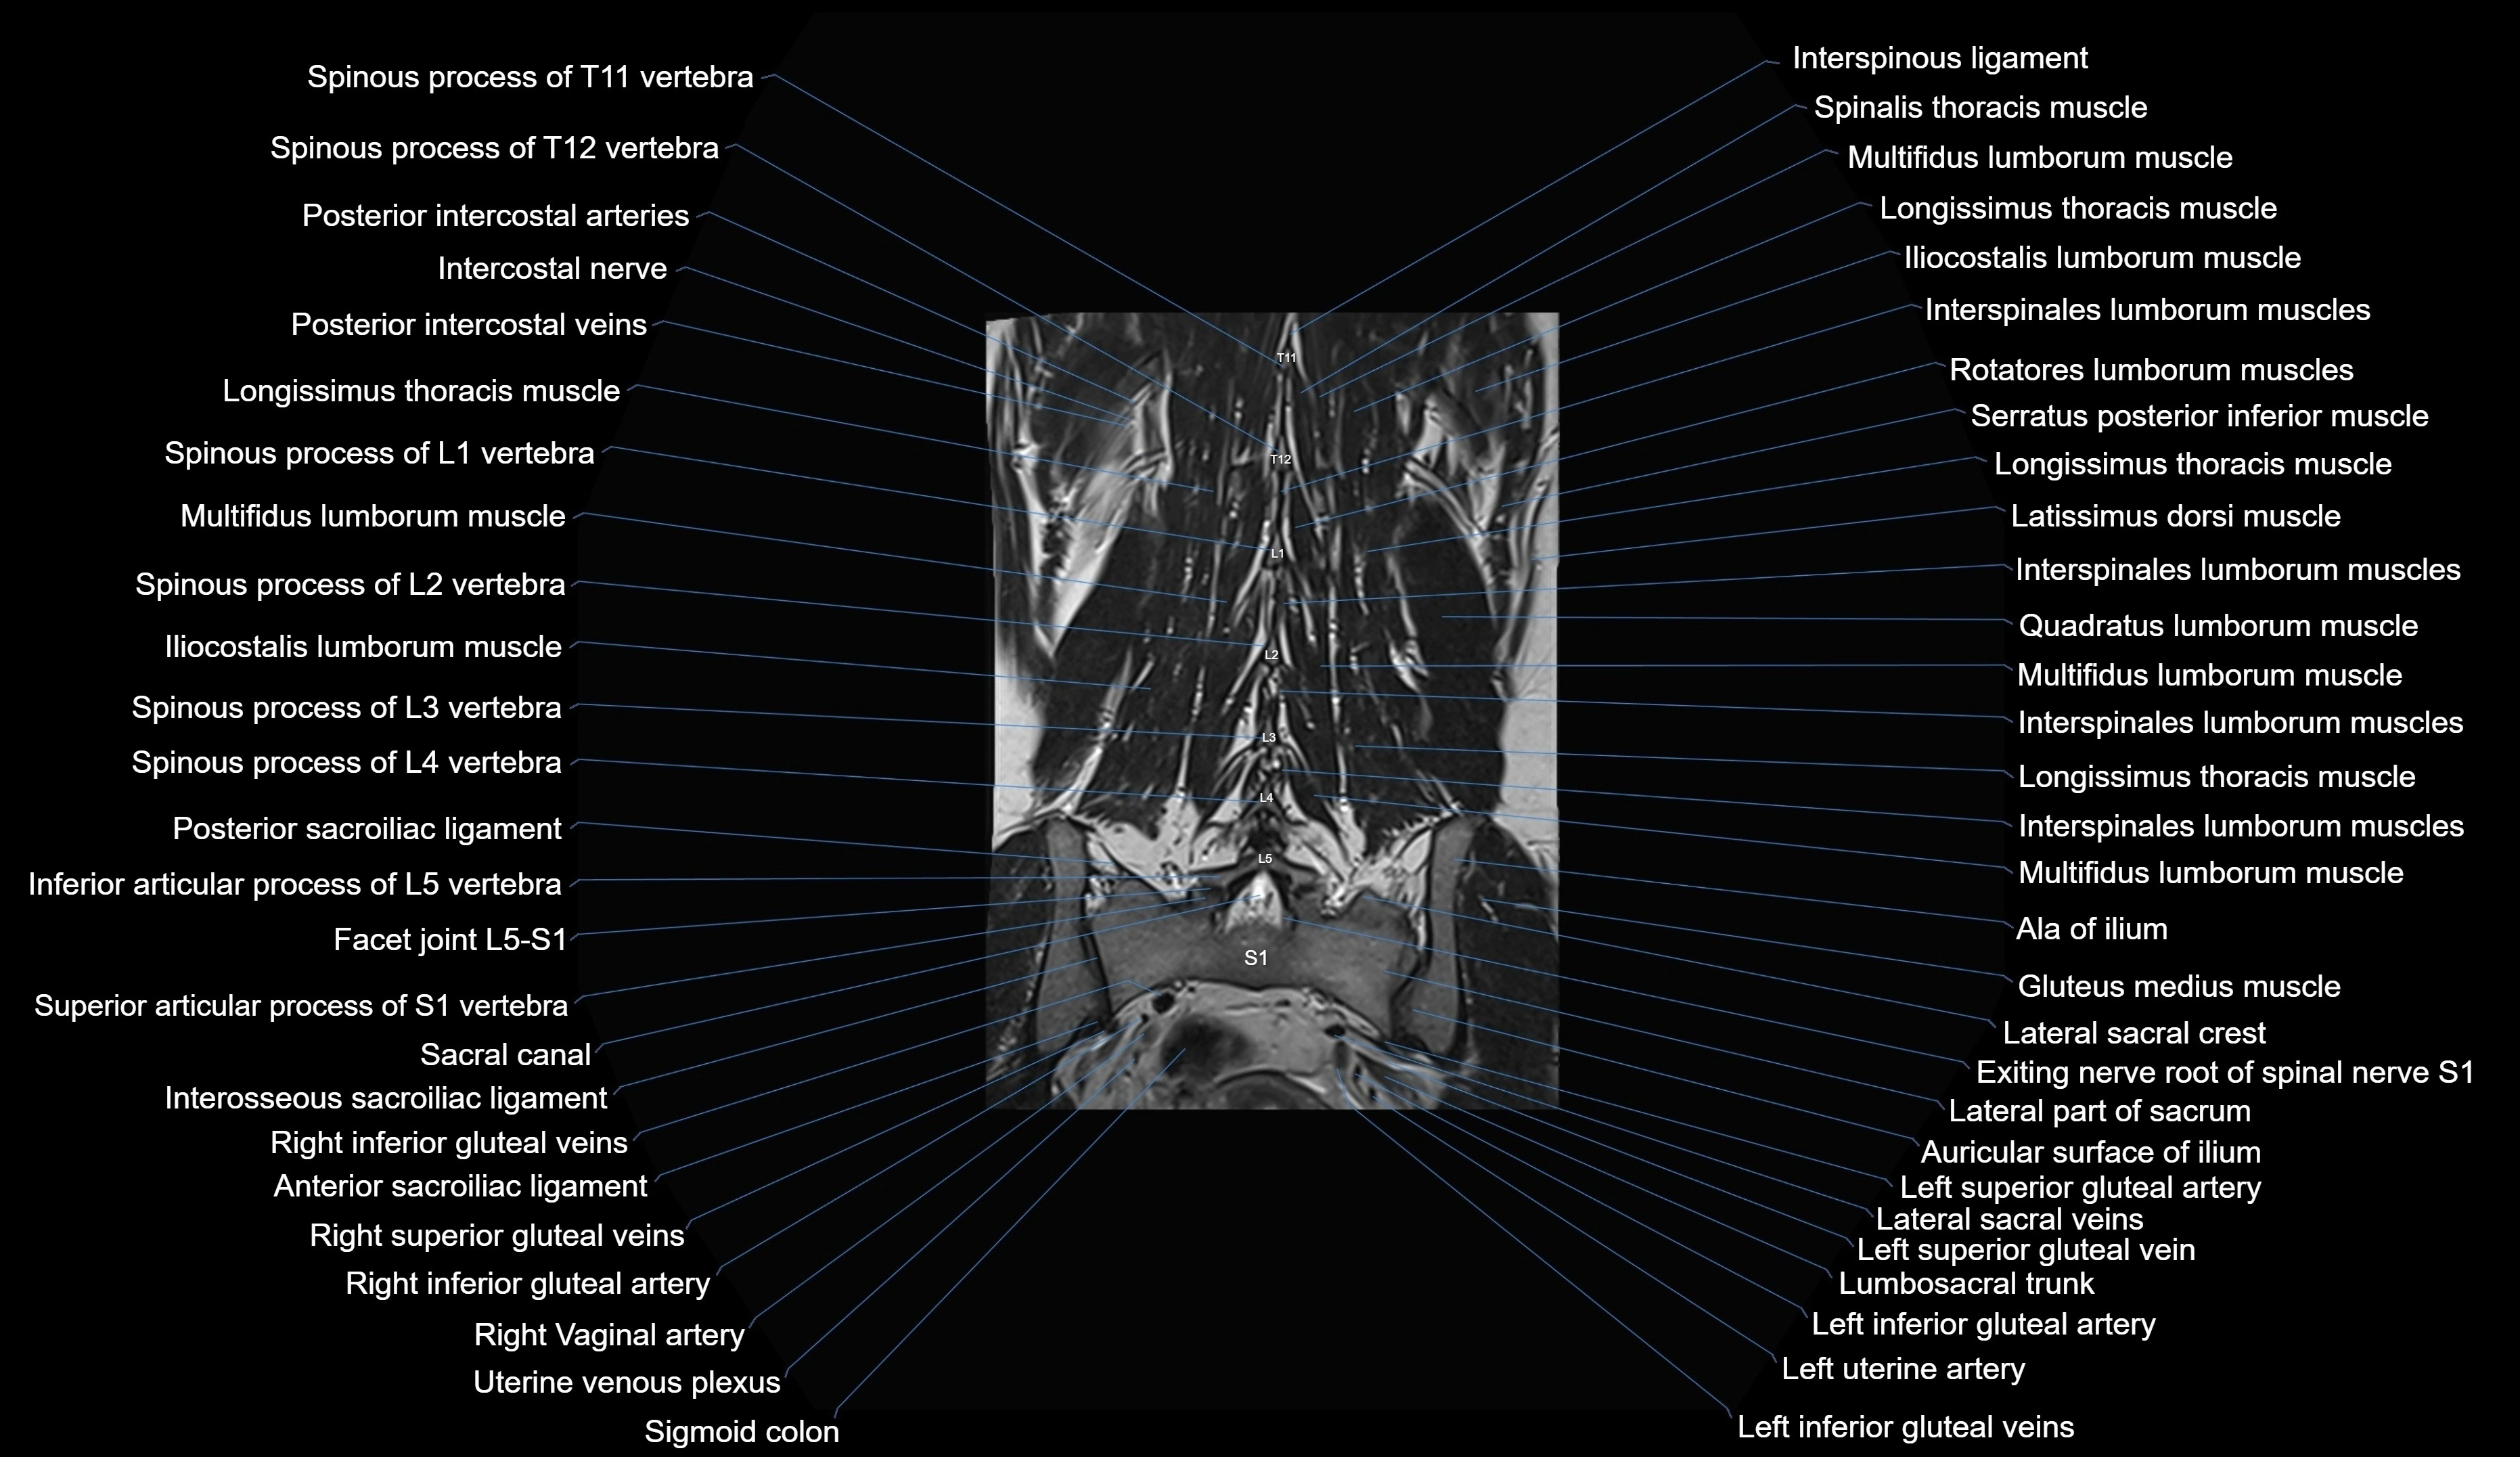

MRI images